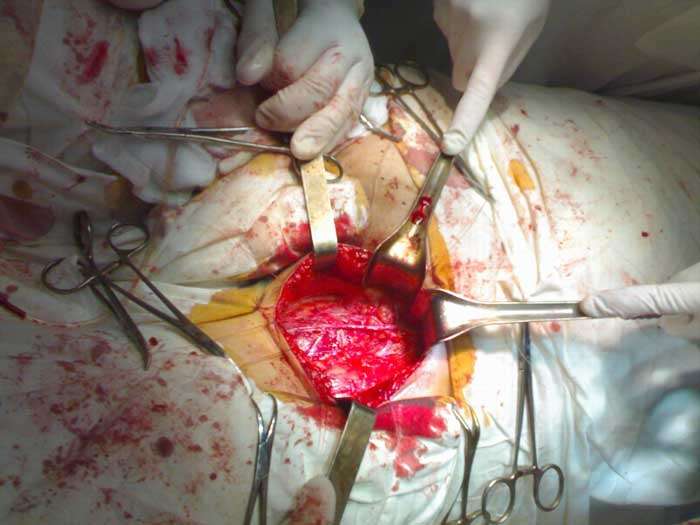

Prostat bezining masofaviy shishi (diametri 65 mm) Bundan tashqari, jinsiy zaiflik prostatit bilan kasallangan har bir erkakda 100% holatlarda sodir bo'ladi. Kimdadir ertaroq, kimdadir kechroq, biroq baribir sodir bo'ladi.

Muammo shundaki, bemor erkaklarning aksariyati shifokorlardan yordam so'rashmaydi. Ba'zilari buni xavfli deb hisoblasa, ba'zilari sharmandalik deb qarashadi. Natijada, biz bemorlar kasallikni rad etadigan holatga tushamiz. Ular yordam so'rashganda ham, ko'p hollarda kechikib so'rashadi va saraton o'smasi rivojlangan bo'ladi.

+ Rasmni ko'rsatishProstatitning juda xavfli kasallik ekanligini tushunishimiz kerak, chunki uning asosiy xavflaridan biri prostata bezi saratoniga aylanishidir. Bu esa, o'z navbatida, ko'pincha bemorni o'limga olib boradi. Nazoratsiz va davolanishsiz qolgan kasallik, ba'zida juda tez rivojlanib 1-2 yil ichida saraton paydo bo'lishiga olib keladi.